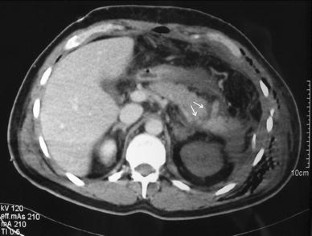

Eleven patients (2 with grade I injury, 3 with grade II injury, and 6 with grade III injury, all diagnosed by contrast-enhanced helical CT) were included. Nonsurgical management was carried out in all of these patients. Among grade III patients, one developed a peripancreatic abscess; another, a pancreatic fistula. Both were successfully treated nonoperatively. The average length of hospital stay was similar in grade I-II and grade III patients. After a median follow-up of 57 months no mortality or pancreatic sequelae had occurred.

Fig. 2